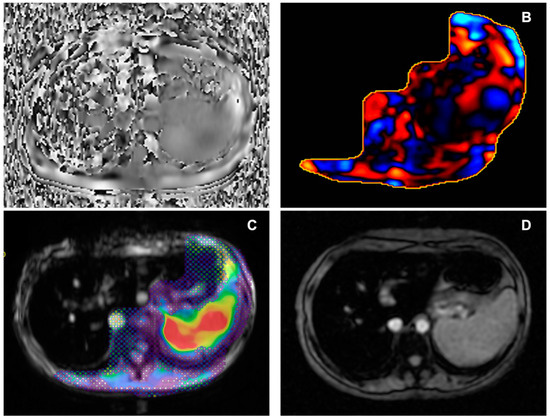

Figure 2. Female, 33 years old, with NASH and hepatic fibrosis (7.4 kPa). (A) Axial magnitude image showing the signal void in the right anterior abdominal subcutaneous tissues. (B) Phase image showing waves propagating through liver tissue. (C) Wave image showing wave propagation, with waves moving parallel to the liver surface, thicker than those in non-fibrotic liver. (D) Corresponding colour elastogram, with free-hand ROI placed in the liver tissue not covered by the 95% confidence map; the colours red and orange are associated with elevated stiffness values. NASH: non-alcoholic steatohepatitis; kPa: kilopascals; ROI: region of interest.

Figure 3. Male, 69 years old, with multiple metabolic risk factors and l grade hepatic fibrosis (2.9 kPa). (A) Axial magnitude image showing the signal void in the anterior abdominal subcutaneous tissues. (B) Phase image showing waves propagating through liver tissue. (C) Wave image showing wave propagation, with thin waves moving parallel to the liver surface. (D) Corresponding colour elastogram, with free-hand ROI placed in the liver tissue not covered by the 95% confidence map; the colour blue is generally found in non-fibrotic or low-grade fibrosis stiffness values. kPa: kilopascals; ROI: region of interest.